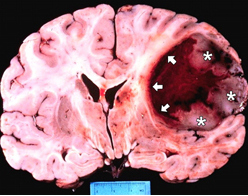

Meyer akut spinal yaralanmalı olgular serisinde %42.9 oranında multıpl travma olduğunu bildirmiştir. Apuzzo ve ark. 45 olguluk

serilerinde olguların %17.8’inde serebral kotüzyo , % 9.8’inde kraniyal fraktür, % 4.4 ünde pulmoner, %4.4’ünde abdominal yaralanma

olduğunu bildirmişlerdir(14).Bizim olgularımızın; %6.9 serebral lezyon , %11.6 toraks patolojisi, %2.3 multipl extremite fraktürü varken

%79 ek bir patoloji yoktu.

Amerika’da motorlu taşıt kazaları sonucu medulla spinalis yaralanmaları sonucu yılda 6000 kişinin öldüğü rapor edilmiştir.Burney

ve ark çalışmasında spinal yaralanmalı hastaların hastane mortalitesi %17 olarak bildirilmiştir(10).1999 yılında KTÜ İlk ve Acil Yardım

Anabilm Dalında yapılan epidemiyolojik bir çalışmada; 651 travma hastasının 39’u(%6) spinal travma olup mortalite % 5.1 olarak

bulunmuş idi . Bu çalışmada ise mortalite % 6.9 olarak bulundu.

4.Omurilikte zararlanmaların oluşmasıFelç riski taşır. Tekrar operasyon gerektirebilir.